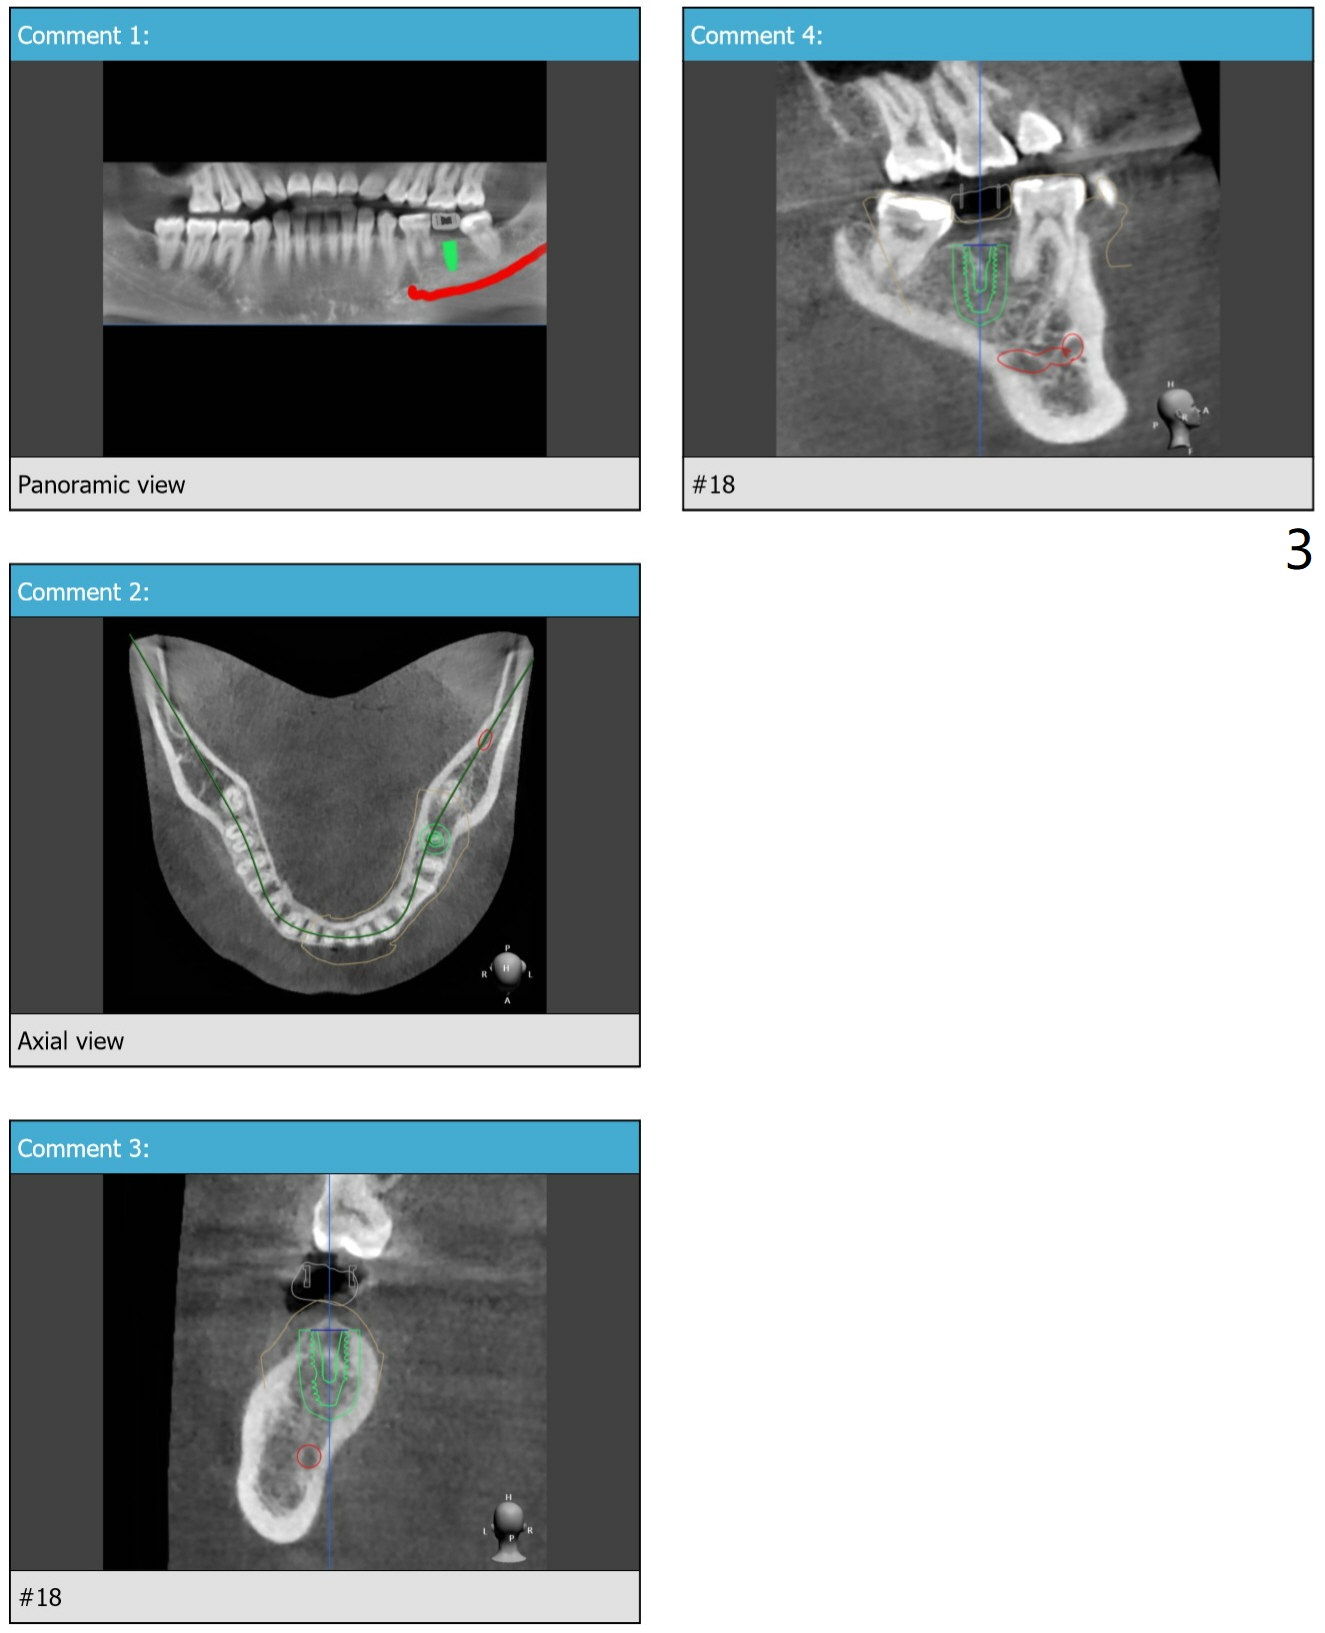

A 25-year-old woman. For sinus lift, 9 mm offset will be used from now on so that DIO sinus approach kit can be applied. Get ready water lift.

Lower Molar

Immediate Implant,

Trajectory II